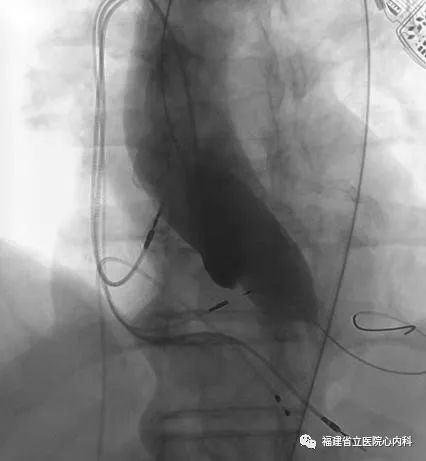

病例1

该病例主动脉瓣为功能性二叶瓣,瓣叶增厚且重度钙化,主动脉根部整体结构大需植入最大型号的人工瓣膜,患者升主动脉增宽且为横位心,增加了大瓣膜植入的难度,术者通过术前CT的精准评估,制定了对应的介入治疗策略,最终在术者稳当的控制下,Venus A- L32瓣膜精准地锚定在预期位置,术后患者症状明显改善。

瓣环

窦部

植入L32瓣膜